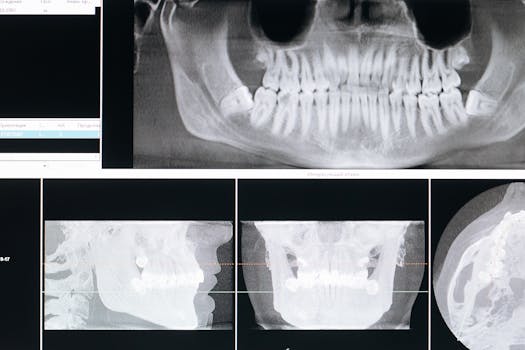

醫師評估是否適合 All on 6,會參考患者的顎骨密度、健康狀況與生活習慣,透過 3D 電腦斷層(CBCT)及數位導引,確保手術安全與準確。

- 初診評估與拍攝3D影像